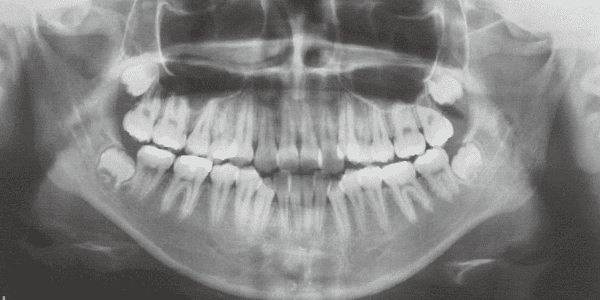

1 At start of treatment 7-21-’88

A case of diverted and cross bite during the deciduous dentition. Despite early treatment, the deviation progressively worsened with age, necessitating surgical treatment. At the initial visit, the patient had a deciduous dentition, and observation was planned (3). With the eruption of the permanent incisors, the mandible shifted slightly to the right, resulting in a cross bite (1) At this point, asymmetry can be confirmed in the front view. However, it is slight. The cephalometric X-ray reveals a structure with a slightly dominant mandible, but asymmetry in the mandibular ramus is not observed.

On the lateral cephalometric radiograph, the vertical height of the face appears greater than its depth. The lower facial height is also high, suggesting a shape somewhat prone to developing a protruding lower bite, though this does not raise significant concern (6). The facial photograph of front view shows slight asymmetry in the face, but it is not particularly extreme (1). The first phase of treatment corrected the anterior cross bite and deviation, but subsequent growth exacerbated the mandibular deviation, necessitating surgical treatment.